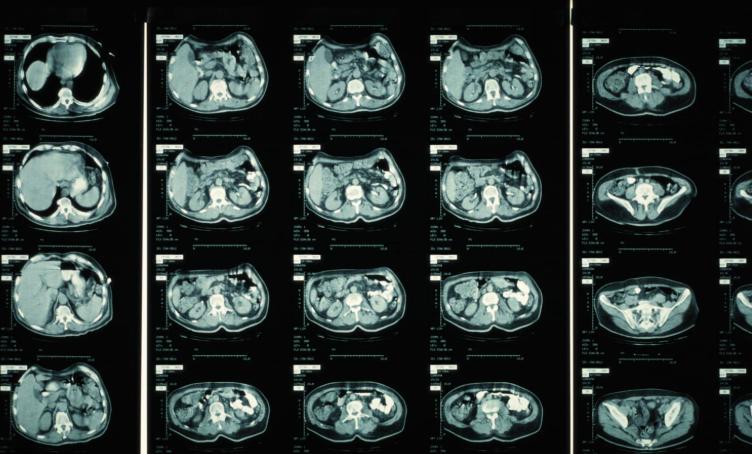

CT也叫“计算机断层扫描”,利用波长短、穿透力强的X射线束对人体部位进行断层扫描,探测器接收反射的X射线信号,然后将其转化为电信号。经过计算机处理后,就可以建立人体内部器官和组织图像,这样医生就可以根据图像来诊断疾病。

当检查开始时,发射球管会发出极细的扇形或锥形X射线束穿透人体特定部位。由于人体内的骨骼、肌肉、体液、器官等等对X射线的吸收程度不同,如此一来探测器接收到信号强弱也不一样。虽然CT图看起来人体是透明的,但是各组织的明暗程度不一,有清晰的轮廓。不过,只从一个角度拍摄,无法实现三维空间的定位,得到的只能是模糊的二维重叠影像。